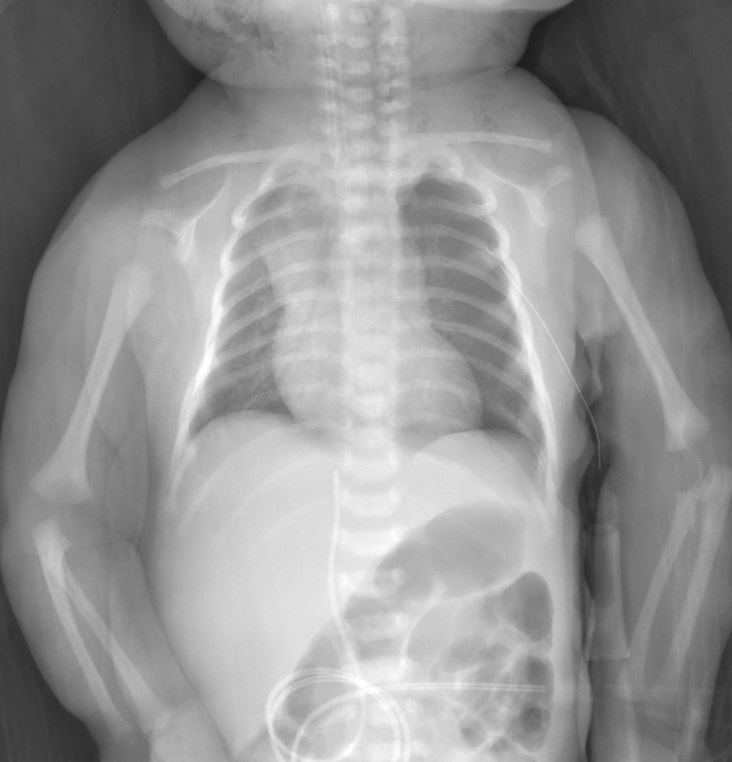

A robust term newborn weighing 4300 grams develops respiratory distress soon after uncomplicated vaginal delivery. Chest X-ray performed within one hour reveals a significant left-sided pneumothorax with lung collapse. Following urgent chest drain insertion, the follow-up radiograph confirms successful resolution and lung re-expansion. This newborn pneumothorax X-ray case emphasizes the need for rapid diagnosis and intervention in neonatal air leak syndromes to prevent deterioration in otherwise healthy term infants.

Left Hemithorax Hyperlucency The initial radiograph demonstrates increased radiolucency over the left chest compared to the right side, caused by free air in the pleural cavity. This lack of normal pulmonary vascular markings is a hallmark sign indicating the presence of pneumothorax in the newborn.

Collapsed Left Lung The left lung appears markedly compressed and retracted medially, with a visible visceral pleural line separating the collapsed lung from the surrounding free air. This collapse results from loss of negative intrapleural pressure, leading to impaired gas exchange and respiratory distress.

Mediastinal Shift to the Right The cardiac silhouette and mediastinal structures show deviation toward the right side due to pressure from the left pneumothorax. In tension pneumothorax, this shift can impair venous return, making prompt recognition and treatment essential.

Chest Drain Tube in Left Chest The post-insertion X-ray clearly shows the radiopaque chest drain positioned within the left hemithorax, typically inserted in the anterior or mid-axillary line. The tube facilitates evacuation of trapped air, allowing the lung to re-expand against the chest wall.

Re-expanded Left Lung Fields After chest drain placement, the left lung demonstrates improved aeration with restoration of normal lung markings and volume. The previously hyperlucent left hemithorax now matches the right side more closely, confirming effective resolution of the pneumothorax.

Normalized Mediastinal Position The heart and mediastinum return to a more central position following successful drainage. This indicates relief of tension and improved cardiopulmonary stability in the neonate.

Newborn pneumothorax is a potentially serious air leak condition that can occur even after normal vaginal birth in term infants. In this case involving a 4300-gram baby, respiratory distress prompted early imaging that identified left-sided pneumothorax with significant lung collapse. Chest drain insertion on the affected left side led to rapid healing, as evidenced by the follow-up X-ray showing re-expansion. Understanding the radiographic signs is crucial for neonatologists and pediatricians managing similar presentations.

Key findings include unilateral hyperlucency without lung markings, a sharp pleural line outlining the collapsed lung, and contralateral mediastinal shift. In supine neonates, air may collect anteriorly, sometimes requiring additional views for confirmation. The initial image here shows classic left pneumothorax features with collapsed left lung, while the second image post-drainage demonstrates the chest tube in the left chest and healed, re-expanded lung fields.